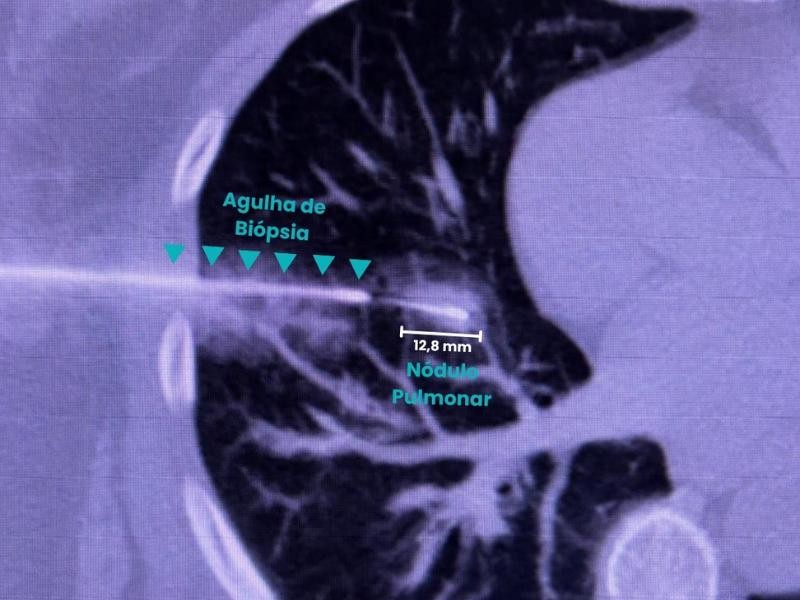

A Biópsia Guiada por Imagem é um procedimento minimamente invasivo que utiliza tecnologias como ultrassom, tomografia computadorizada ou ressonância magnética para orientar a introdução de uma agulha de biópsia até o local exato da lesão. Essa precisão é o que permite a coleta segura de amostras para análise laboratorial. A Biópsia Guiada por Imagem é realizada com equipamentos de última geração, garantindo conforto e segurança do paciente. Além disso, a técnica reduz a necessidade de cirurgias abertas e acelera o diagnóstico, sendo essencial para identificar tumores, infecções e doenças inflamatórias.

Durante a Biópsia Guiada por Imagem, o paciente é posicionado de forma estratégica, e o médico radiologista intervencionista utiliza imagens em tempo real para direcionar a agulha até o ponto exato do tecido ou amostra a ser coletado.

• Biópsia por Agulha Grossa (Core Biopsy) – Retira fragmentos de tecido, ideal para tumores sólidos.

Enquanto uma cirurgia pode demandar anestesia geral e cortes, a Biópsia Guiada por Imagem usa uma agulha de biópsia e é realizada sob anestesia local.